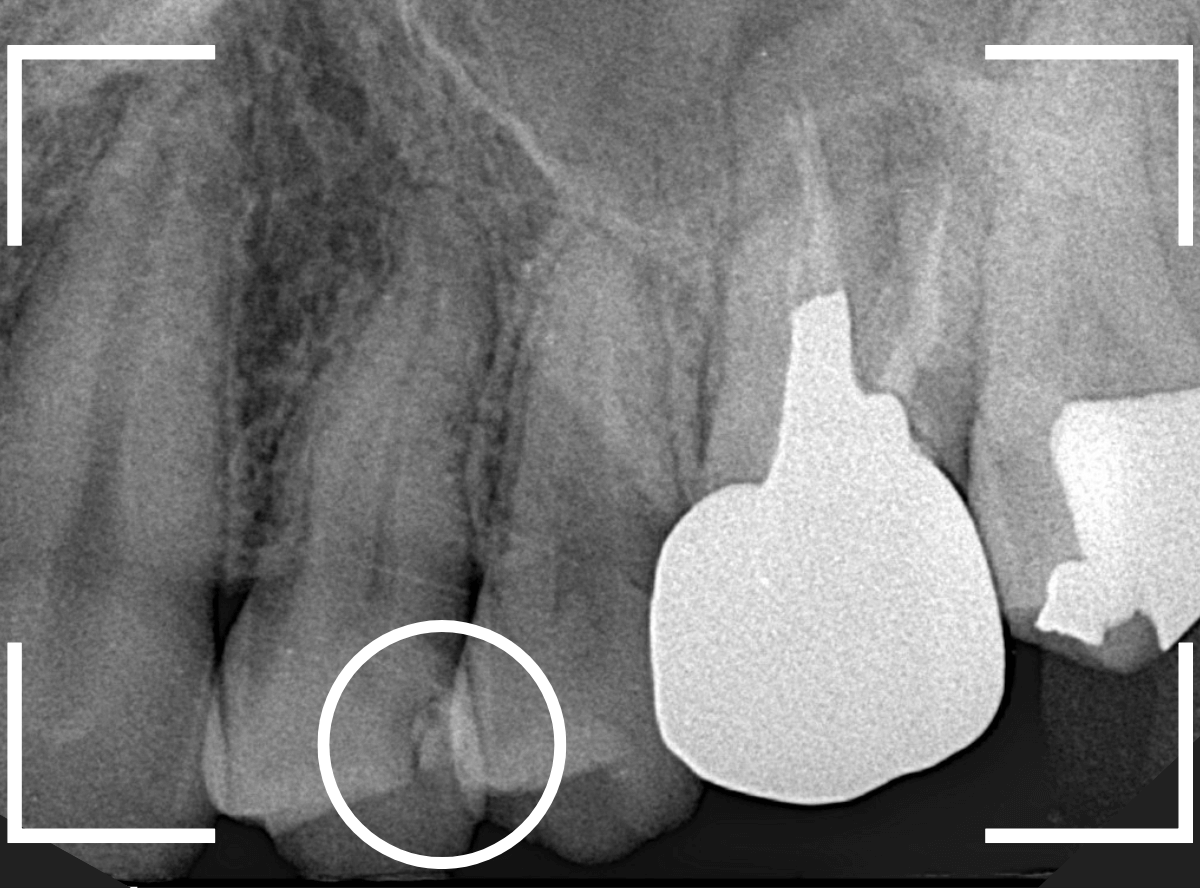

レントゲン写真を撮影しました。

青い線が神経

黄色い線がレジン

赤い線が虫歯

です。

思ったよりも深い虫歯をレジンで埋めてあったようで、さらにその中が虫歯になっている状況です。

神経までかなり近い虫歯と思われます。

症状はありません。